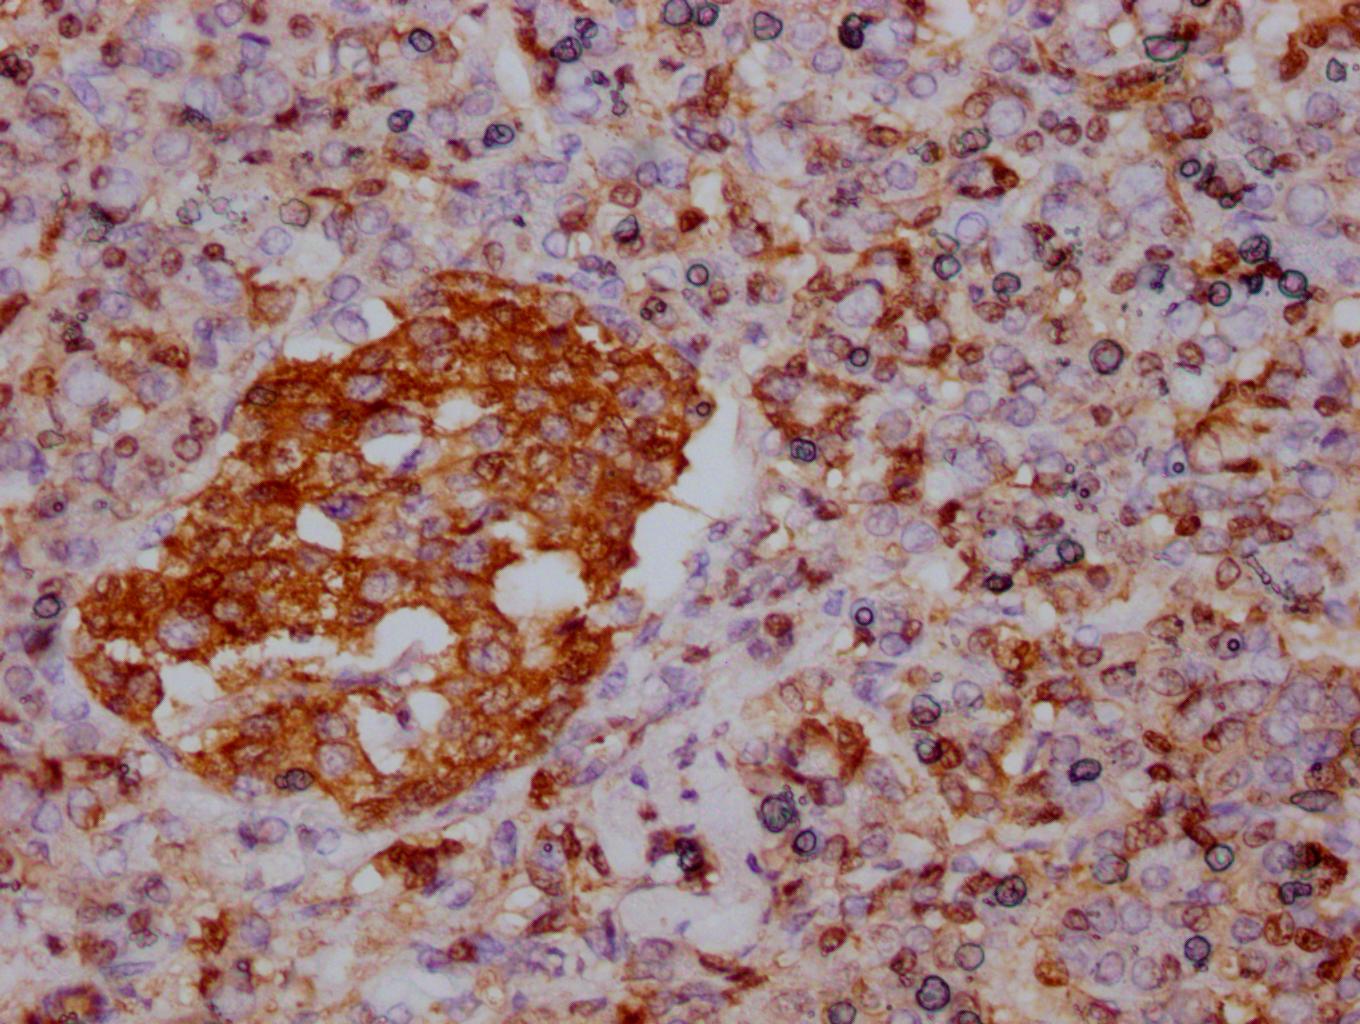

IHC image of CSB-MA007670A0m diluted at 1:500 and staining in paraffin-embedded human pancreas tissue performed on a Leica BondTM system. After dewaxing and hydration, antigen retrieval was mediated by high pressure in a citrate buffer (pH 6.0). Section was blocked with 10% normal goat serum 30min at RT. Then primary antibody (1% BSA) was incubated at 4°C overnight. The primary is detected by a biotinylated secondary antibody and visualized using an HRP conjugated SP system.